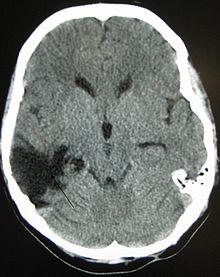

A CT of the head years after a traumatic brain injury showing an empty space where the damage occurred marked by the arrow.

Improvement of neurological function usually occurs for two or more years after the trauma. For many years it was believed that recovery was fastest during the first six months, but there is no evidence to support this. It may be related to services commonly being withdrawn after this period, rather than any physiological limitation to further progress.[9] Children recover better in the immediate time frame and improve for longer periods.[10]

Complications are distinct medical problems that may arise as a result of the TBI. The results of traumatic brain injury vary widely in type and duration; they include physical, cognitive, emotional, and behavioral complications. TBI can cause prolonged or permanent effects on consciousness, such as coma, brain death, persistent vegetative state (in which patients are unable to achieve a state of alertness to interact with their surroundings),[137] and minimally conscious state (in which patients show minimal signs of being aware of self or environment).[138][139] Lying still for long periods can cause complications including pressure sores, pneumonia or other infections, progressive multiple organ failure,[94] and deep venous thrombosis, which can cause pulmonary embolism.[22] Infections that can follow skull fractures and penetrating injuries include meningitis and abscesses.[94] Complications involving the blood vessels include vasospasm, in which vessels constrict and restrict blood flow, the formation of aneurysms, in which the side of a vessel weakens and balloons out, and stroke.[94]